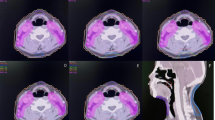

A total of 17 cases (17/132, 12.9%, crude rate) developed MRI-indicated TLI. The baseline characteristics of these patients are summarized and compared with those of patients without TLI in Table 1. Of the 17 cases, 13 (76.5%) and 4 (23.5%) had radiation-induced injuries to the unilateral and bilateral TLs, respectively. Two cases simultaneously developed radiation-induced brain stem damage (contrast-enhanced lesions were evident on post-contrast T1-weighted images). Of the 17 patients who developed TLIs, 8 exhibited varying degrees of clinical symptoms, such as vertigo, headache, memory deterioration, muscle weakness, and personality changes; the remaining 9 patients were asymptomatic. Overall, the MRI findings in the TLI patients revealed a continuous spectrum of RT-associated damage. Small solid enhanced nodules were evident in five cases, while moderate and large lesions were apparent in seven and five cases, respectively (lesions were classified as described in ref. 16). The outcomes of TLI evolution were documented; the MRI features of TLI (including signal abnormality on T1 and T2 images) resolved completely in four patients following gradual improvement over a few years. In contrast, one patient developed a large contrast-enhanced lesion, with a central necrotic core, in the right TL, accompanied by severe white matter lesions with a large confluent area that extended superiorly and caused a mass effect. This was the only patient to die from TLI. Apart from one T2 case who had not received chemotherapy, all other TLI patients were of stage T3 (6 cases) or T4 (10 cases) and underwent chemotherapy during their treatment periods. Data from a representative TLI case, and the corresponding dose distributions, are shown in Fig. 1. The median TLI latency period was 43 months (range, 19–68 months). The overall TLI-free survival rate was calculated using the Kaplan-Meier procedure (Fig. 2); the actuarial TLI-free survival rates were 95.5% and 85.8% at 3 and 5 years, respectively.